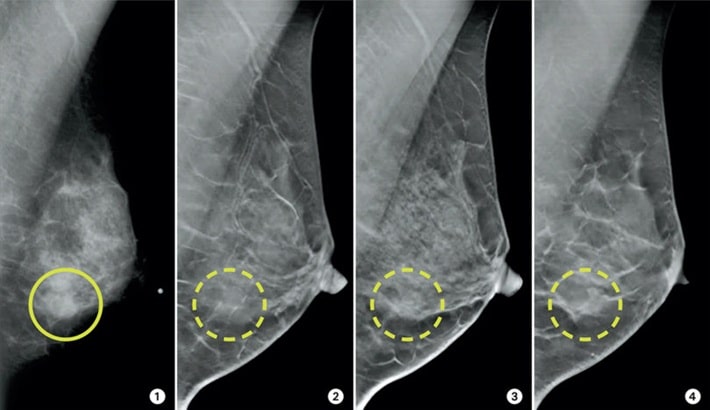

ماموگرافی برای زنان با سینههای متراکم

زنانی که بافت سینه متراکم دارند، بیشتر در معرض خطای تشخیص هستند. برای این دسته افراد، مراجعه به یک مرکز ماموگرافی مجهز اهمیت دوچندان دارد. در مرکز تصویربرداری تابا از تکنیکهای ویژهای استفاده میشود که امکان مشاهده ضایعات پنهان در بافت متراکم را فراهم میسازد.

دستگاه ماموگرافی وظیفه دارد کوچکترین تغییرات در بافت سینه را آشکار کند. اگر دستگاه از وضوح کافی برخوردار نباشد؛ ممکن است ضایعات کوچک یا میکروکلسیفیکاسیونها (ذرات ریز کلسیم که اولین نشانههای سرطان پستان هستند) دیده نشوند. این موضوع میتواند تشخیص را به تعویق بیندازد و روند درمان را سختتر کند. بنابراین کیفیت دستگاه مستقیماً با نجات جان بیمار ارتباط دارد.

در گذشته ماموگرافیها با سیستم آنالوگ انجام میشدند که تصاویر کیفیت پایینتری داشتند. اما امروز ماموگرافی دیجیتال امکان بررسی جزئیترین بخشهای سینه را با وضوح بسیار بالا فراهم کرده است. در یک مرکز ماموگرافی که از تجهیزات دیجیتال استفاده میکند، احتمال تشخیص زودهنگام بیماری چند برابر بیشتر است. مرکز تصویربرداری تابا نیز با بهرهگیری از همین تکنولوژی بهروز، توانسته دقت تشخیص را به حد چشمگیری افزایش دهد.